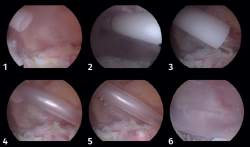

La técnica quirúrgica consistió en realizar en todos los pacientes una artroscopia de hombro con posición en silla de playa. Se utilizó profilaxis antibiótica pre- y posquirúrgica con cefazolina. Se realizaron los portales posterior y lateral subacromial, se hizo un desbridamiento de la bursa subacromial y la tenotomía de la porción larga del bíceps mediante el uso de un vaporizador en todos ellos. En el grupo del balón subacromial asociado (balón InSpace® de Stryker, Michigan, USA), se realizó antes de su implantación la medida del tamaño de este de entre los 3 tamaños posibles, midiendo aproximadamente desde 1 cm medial al borde glenoideo hasta la región lateral del troquíter. Posteriormente, se introdujo el implante a través del portal lateral y se rellenó con suero salino estéril hasta el límite recomendado según la técnica quirúrgica (desde 9 a 24 cm3 en función del tamaño seleccionado del balón). Posteriormente, se liberó el balón tras comprobar previamente su correcta posición por encima de la glena y 2 cm sobre el muñón del tendón del manguito rotador y su estabilidad observando que no interfiere con las maniobras pasivas de rango de movimiento del hombro del paciente (Figuras 1 y 2).

Figura 2. Proceso de colocación del balón subacromial por vía artroscópica a través del portal lateral subacromial.